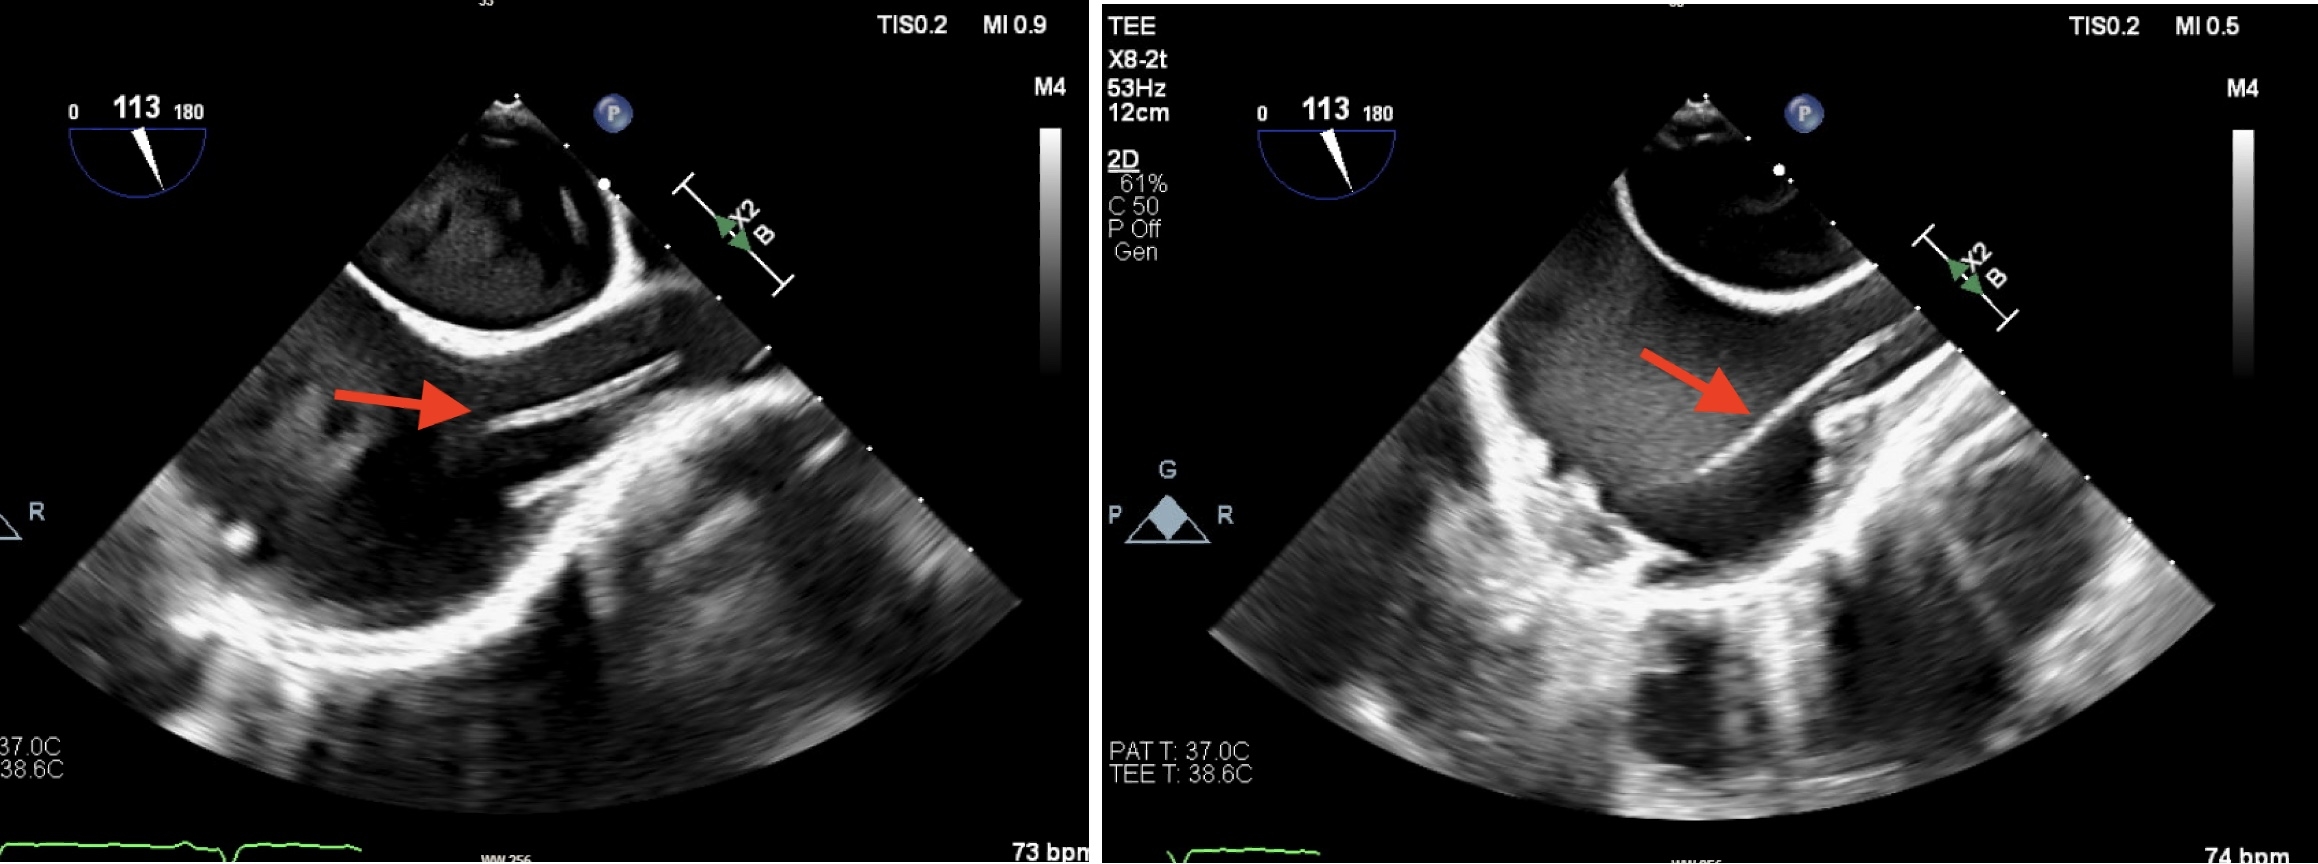

33-year-old female with a history of polysubstance IV drug abuse, hepatitis C infection, multiple hip surgeries with abscess drainage, tricuspid valve endocarditis with MRSA bacteremia, treated with IV Ceftaroline and daptomycin for 6 weeks via left PICC line, which was removed 2 weeks before her hospital presentation. The patient presented to the hospital with complaints of fever and generalized weakness, she was treated with broad-spectrum antibiotics, and investigations with TEE revealed mobile Tricuspid valve vegetation as well as a linear, highly mobile, tubular structure within the SVC extending into the right atrium, presenting a GFCS. CT chest also revealed multiple septic emboli, and blood cultures were positive for Serratia marcescens and ESBL Klebsiella pneumoniae. Patient was started on Anticoagulation with Eliquis and was evaluated by the Cardiothoracic surgery team for possible AngioVac, yet no good targets were found, and a decision was made to treat the patient medically without placing any further central lines. Unfortunately patient had signed out AMA after 1 week before completing her antibiotics course, yet she continued to take Eliquis outpatient. Patient returned to our Center 2 months later with similar complaints, TTE revealed large 3.8 * 2.35 cm highly mobile, irregularly shaped Tricuspid Valve mass that has significantly increased in size in comparison with prior imaging, and complete resolution of the previosly seen GFCS, Patient again left AMA refusing further treatments and investigations.

Ghost fibrin catheter sheath (GFCS) is a rare condition that can sometimes be a harmless incidental finding. However, it may also pose a risk of thrombosis and embolization, particularly in the context of infective endocarditis. While definitive treatment guidelines are lacking, antibiotics and anticoagulation are commonly used. AngioVac has been used in some instances, but its clear benefits has not been established. Our case demonstrated complete resolution of the GFCS with anticoagulation despite not being compliant with antibiotics.